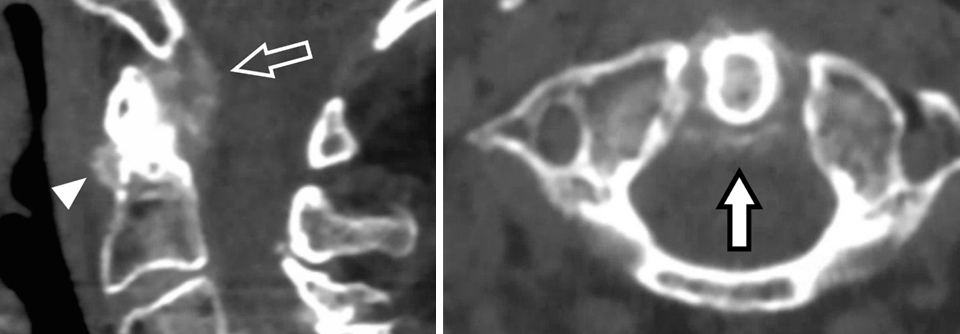

Ob eine Person Nackenschmerzen entwickelt, scheint neben einer genetischen Prädisposition von individuellen anatomisch-biologischen, psychologischen, sozialen sowie beruflichen Faktoren abzuhängen. Für das diagnostische und therapeutische Management ist entscheidend, ob es sich um neuropathische oder um nicht-neuropathische Schmerzen handelt, führen der Neurologe Dr. Steven­ Cohen­ von der Johns Hopkins Scool of Medicine in Baltimore und der Psychiater Dr. W. Michael­ Hooten von der­ Mayo Clinic School of Medicine in Rochester aus. Neuropathische Schmerzen entstehen durch Nervenwurzelkompressionen (Bandscheibenvorfall, Foramenstenose), eine Spinalkanalstenose oder eine zervikale…